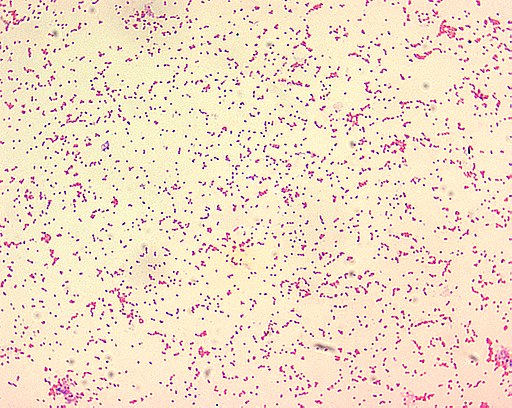

Brucella melitensis je gram-negativní kokovitá bakterie z rodu Brucella. Jedná se o nepohyblivou, striktně aerobní, kataláza pozitivní bakterii, která se kultivuje na tryptonovém nebo Brucella agaru při atmosféře 10 % CO2. Je původcem brucelózy ovcí a koz. Nakazit se mohou velbloudi, skot, pes nebo člověk. Vyskytuje v celkem 3 různých biovarech, převažuje biovar 1. Wikipedia

Brucella melitensis je gram-negativní kokovitá bakterie z rodu Brucella. Jedná se o nepohyblivou, striktně aerobní, kataláza pozitivní bakterii, která se kultivuje na tryptonovém nebo Brucella agaru při atmosféře 10 % CO 2.

Brucella melitensis is a Gram-negative coccobacillus bacterium from the Brucellaceae family. The bacterium causes ovine brucellosis, along with Brucella ovis.

Brucella melitensis je gramnegativní kokobacilární bakterie, která produkuje zoonotické onemocnění zvané brucelóza ovcí a koz. Infekce způsobuje značné ekonomické ztráty způsobením potratů ovcí a koz.